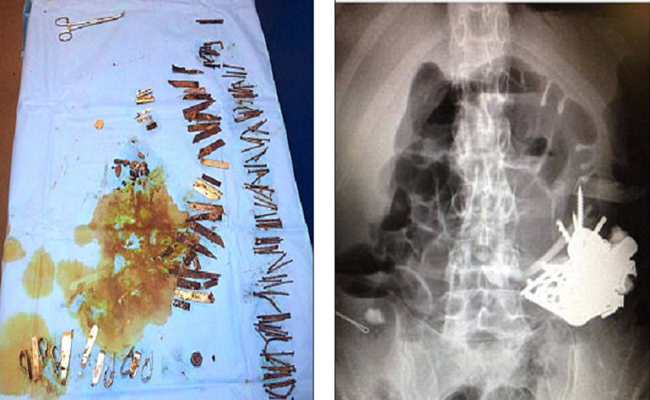

خضع رجل فرنسي يبلغ من العمر 52 عاما لعملية جراحية من أجل إزالة قطع معدنية موجودة في معدته، بعد أن بدأت بإحداث ثقوب في الجهاز الهضمي.

وقضى هذا الرجل سنوات عدة في ابتلاع الأدوات المعدنية، بسبب اضطرابه النفسي. وفي نهاية المطاف، تجمعت القطع معا داخل جسده، وشكلت كتل تسمى “البازهر” (وهي أجسام غير قابلة للهضم).

ونُقل المريض إلى غرفة الطوارئ 5 مرات خلال 5 سنوات، لأنه كان يتقيأ دما ويتعرض لألم شديد نتيجة وجود هذه الكتل في بطنه، وفقاً لقناة روسيا اليوم، وخضع أيضا لخمس عمليات تم خلالها إزالة المسامير والسكاكين والمكسرات ورأس مفك البراغي، بالإضافة إلى مقابض الملاعق والحصى وأسلاك الحديد والعملات المعدنية، من بطنه.

وبعد 8 أشهر، نُقل المريض إلى المستشفى للسبب نفسه، ثم خضع للجراحة، حيث وجد الأطباء آثارا للمسامير والسكاكين والأدوات الحادة الأخرى في بطنه. كما زار المستشفى 3 مرات أخرى بين عامي 2013 و2016.